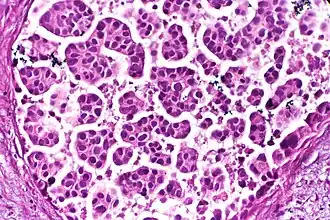

The most commonly used stain in histology is a combination of hematoxylin and eosin (often abbreviated H&E). Hematoxylin is used to stain nuclei blue, while eosin stains the cytoplasm and the extracellular connective tissue matrix of most cells pink. There are hundreds of various other techniques which have been used to selectively stain cells. Other compounds used to color tissue sections include safranin, Oil Red O, congo red, silver salts and artificial dyes. Histochemistry refers to the science of using chemical reactions between laboratory chemicals and components within tissue. A commonly performed histochemical technique is the Perls' Prussian blue reaction, used to demonstrate iron deposits in diseases like Hemochromatosis.[2]

Architectural pattern of any suspicious cells, in this case nests of cells, as well as components of the intervening stroma. -

Nests: islands of cells of similar type. -